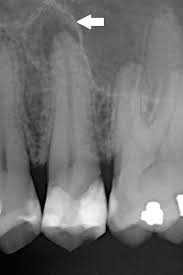

치주염 진단과 검사

치주염(Periodontitis)을 진단하고 검사하는 과정은 치과 전문가에 의해 수행되며 다양한 절차와 도구를 사용합니다. 아래에 치주염 진단과 검사에 대해 자세히 설명하겠습니다:

4. X-레이 검사: 치주염 진단에는 치아 주변 뼈의 손상 정도를 평가하기 위해 X-레이 검사가 사용될 수 있습니다. 이를 통해 의사는 뼈 손상이 어느 정도인지 확인하고 치주염의 정확한 진행 정도를 평가할 수 있습니다.

2. 뼈 손상: 치주염은 치아 주변 뼈에 손상을 일으킬 수 있으며, 이로 인해 뼈의 감소와 조직의 파괴가 발생할 수 있습니다. 심한 경우, 이로 인해 치아를 잃는 결과로 이어질 수 있습니다.